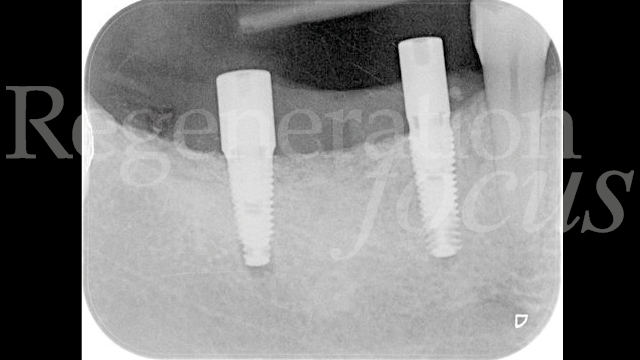

Una paziente di 44 anni, non fumatrice e in buone condizioni di salute generale, si è presentata riferendo significative difficoltà masticatorie, nel quarto quadrante, conseguenti alla perdita del ponte 45-47 per complicanze endodontico-protesiche. L’anamnesi medica non rivelava patologie sistemiche di rilievo né assunzione di farmaci che potessero interferire con i processi di guarigione ossea. L’esame intraorale evidenziava una discreta atrofia della cresta alveolare edentula con collasso vestibolo-linguale dei tessuti molli (Fig. 1). Gli elementi dentari adiacenti presentavano condizioni parodontali stabili. L’analisi radiografica tridimensionale, mediante CBCT, ha permesso una valutazione dettagliata del deficit osseo (Fig. 2). Dopo discussione delle diverse opzioni terapeutiche, inclusa la possibilità di impianti corti, si è optato per una rigenerazione ossea guidata mediante mesh customizzata.

Il follow-up a 2 e 4 settimane ha documentato la guarigione per prima intenzione. A 6 mesi, la CBCT ha evidenziato eccellente integrazione dell’innesto con ottimale densità ossea (Fig. 10). La seconda fase chirurgica ha previsto la rimozione della mesh e l’inserimento simultaneo di due impianti tissue level (3.7 x 10 mm plat. 3.7 in sede 45; 3.7 x 8 mm plat. 4.5 in sede 47) caratterizzati da un design transmucoso concavo di 1.8 mm con superficie anodizzata (Matrix Line, TRI Dental Implants) (Fig. 11). Il torque di inserimento di 45 Ncm ha confermato l’ottima qualità ossea.